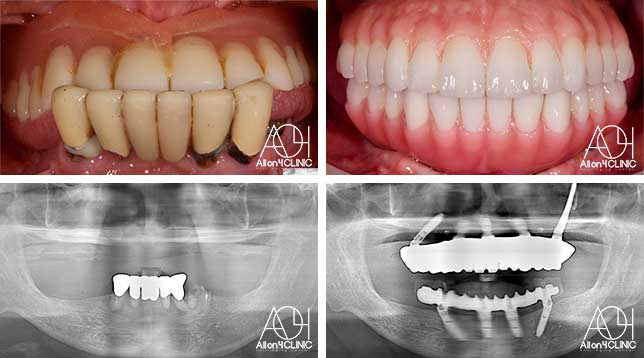

Treatment : All-on-4 zygoma

- Upper All-on-4

- Lower All-on-4

Age : 65 Sex : 男 H.M

| 主訴 | 日本各地のクリニックを受診し、カウンセリングを何回も受けているがどのクリニックで治療を受けるべきか迷っている。 |

| 治療内容 | ガイデッドサージェリーにてインプラント埋入。骨量が少量であったためザイゴマインプラントにて治療 |

| 治療費(総額) | ¥5,200,000(税抜) 『モニター割引適用』 『オリジナル動画撮影協力あり』 |

| リスク | 治療後の口腔管理が不適切な場合、埋入したインプラント周囲に感染・炎症を起こし、脱落する可能性がございます。 |